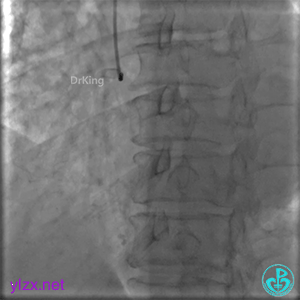

经指引导管造影。

经微导管造影。